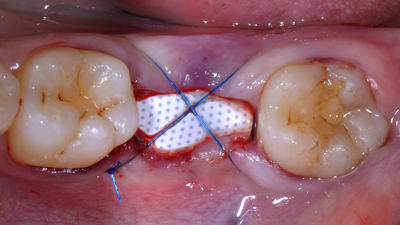

Case Reports Periodontics Implantology Treatment of Peri-implantitis Using a Combined Decontaminative and Regenerative Protocol: Case Report By Nicola Alberto Valente, DDS, Sebastiano Andreana, DDS February 01, 2018 11 min read